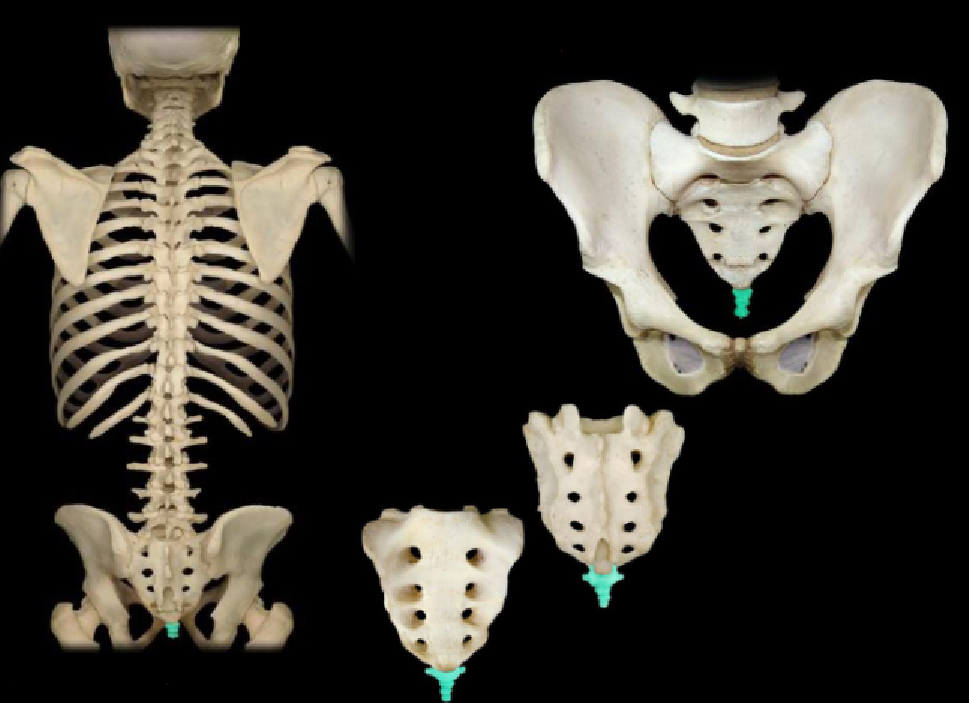

What bone is highlighted in this image?

rib cage (thoracic cage)

What type of ribs are highlighted in this image?

vertebral (false, floating) ribs (the two bottom ribs in the back)

What type of ribs are highlighted in this image?

vertebronchondral (false) ribs (the 3 ribs right above floating)

What type of ribs are highlighted in this image?

vertebrosternal (true) ribs (the spiral looking bones going from behind to the front)

What bone is highlighted in this image?

costal cartilage (medial, touching the sternum)

What bone is highlighted in this image?

coccyx

What bone is NOT highlighted in this image?

sacrum (has 8 holes, is right above the tailbone)